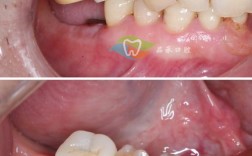

种植牙手术是否需要切开牙龈,主要取决于患者的牙槽骨条件、种植方案及医生采用的技术,目前临床常见的切开方式包括以下三种情况:

传统切开式种植(需切开1-2次)

传统种植牙手术通常需要切开牙龈,暴露牙槽骨后植入种植体,再缝合伤口,若患者骨量不足,可能还需先进行骨增量手术(如植骨或上颌窦提升),这意味着需额外切开一次,传统种植牙可能涉及1-2次切开:

微创不翻瓣种植(无需切开或仅1次)

随着技术的发展,微创种植(不翻瓣技术)逐渐普及,医生通过数字化导板精准定位,直接在牙龈上打孔植入种植体,无需大面积切开,但若术后需二期手术安装愈合基台,则可能需一次小切口。

即刻种植(通常1次切开)

对于符合条件的患者,拔牙后可立即植入种植体,减少一次切开,但若需同期植骨,可能仍需额外切口。